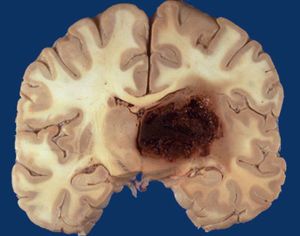

Basal ganglia hemorrhage

This is how a bleeding in the brain looks like!This is a case of hypertensive patient presented with basal ganglia hemorrhage.